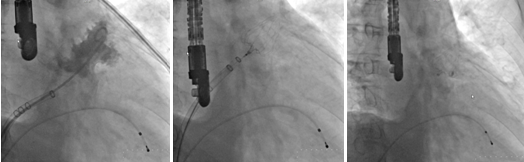

手術(shù)在全麻下進(jìn)行,無(wú)須開刀,僅在右側(cè)大腿股靜脈穿刺一個(gè)針眼,由該針眼植入一根細(xì)導(dǎo)管,由此將手術(shù)器械引導(dǎo)到心臟,隨后進(jìn)行房間隔穿刺,并進(jìn)行左心耳造影。最后,專家為患者植入了一枚左心耳封堵器,經(jīng)效果評(píng)價(jià)封堵良好。手術(shù)獲成功,全程歷時(shí)1個(gè)多小時(shí)。

?????? 左心耳造影圖像???????左心耳封堵器釋放前?????? 左心耳封堵器成功釋放后